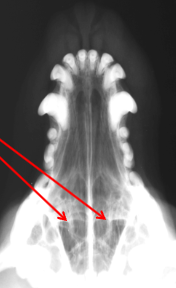

ID Radiographic View

Frontal Sinus View

ID

Frontal Sinus

Ethmoid Turbinates

Maxillary Turbinates

Nasopharynx

Maxillary Recess